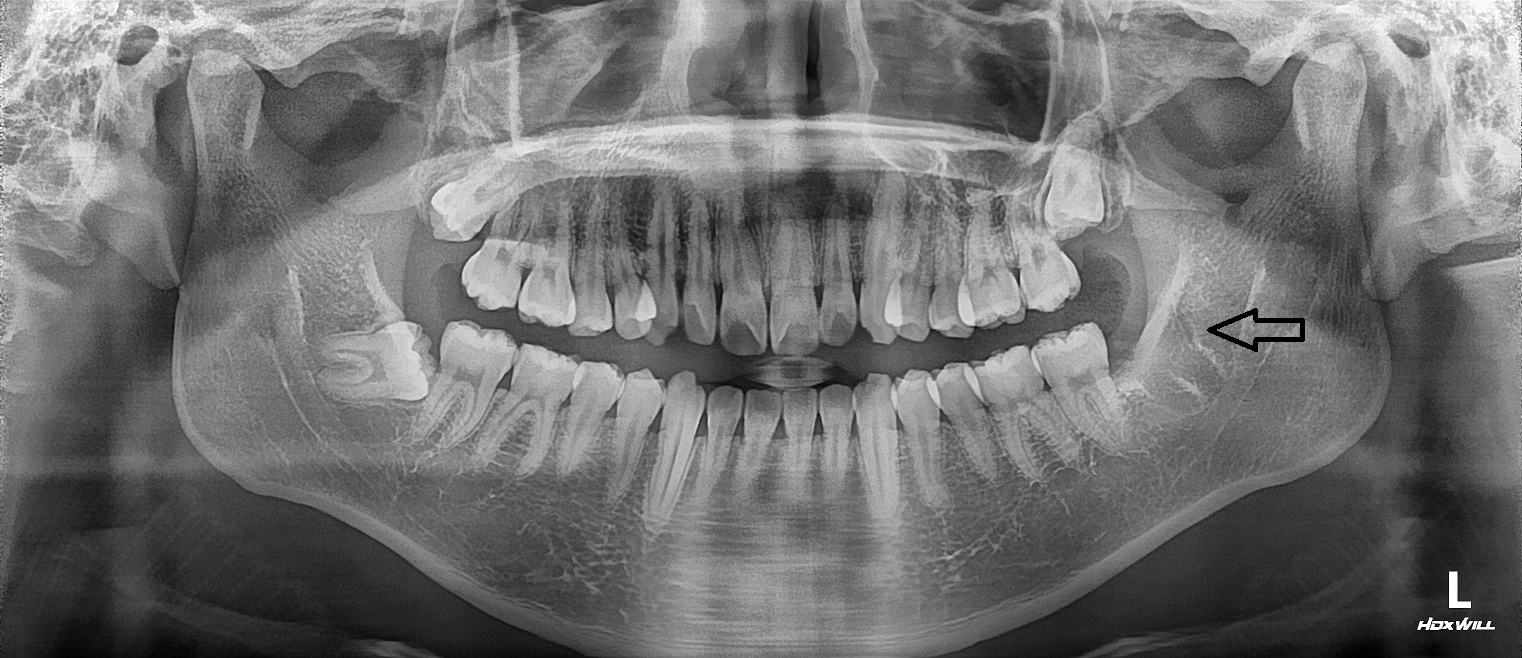

[사랑니발치] 교정치료중인 환자분 사랑니 발치 의뢰되어 온 경우

하악 양쪽 사랑니 발치를 위해 교정치과병원에서 의뢰되어 덴티스킨 치과로 오셨습니다.

두 치아 모두 신경과 가깝고 깊게 수평 매복되어 쉽지 않은 케이스였지만

아주 편안하게 잘 뽑아드려 환자분 만족도가 큰 케이스였습니다.